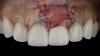

(2.) Preoperative retracted maxillary view of an implant-supported restoration at the site of tooth No. 9 demonstrating a peri-implant soft-tissue dehiscence extending approximately 3-mm apical to the gingival margin of tooth No. 8. Note the thin and erythematous marginal tissue evident at the zenith.

Figure 2

The patient in this case had undergone implant therapy at the site of tooth No. 9 and was restored with a cement-retained restoration more than 5 years prior. At presentation, the site demonstrated a peri-implant soft-tissue dehiscence that extended approximately 3-mm apical to the gingival margin of tooth No. 8. Thin and erythematous marginal tissue was evident at the zenith (Figure 2). The crown was removed, and a partial thickness flap was reflected using a papilla-sparing incision design. This revealed that the implant was positioned too far facially and that its body was visible through a very thin layer of bone (Figure 3 and Figure 4). The first objective of treatment was to minimize the facial extent of the emerging abutment and crown. To accomplish this, the facially positioned abutment and implant crown margin were both recontoured. The second treatment objective was to provide additional supracrestal soft tissue that would more adequately maintain the peri-implant margin. The tuberosity was selected as a donor site due to its dense, high-quality connective tissue, low propensity for shrinkage, and association with minimal patient discomfort. Once the graft was secured (Figure 5 through Figure 7), the flap was coronally positioned (Figure 8). After a healing period of 2 weeks, the margin of tooth No. 9 exhibited an ideal position in relation to its contralateral counterpart and demonstrated increased soft tissue thickness (Figure 9). Three months postoperatively, further healing had improved the esthetics and the position of the margin had been maintained (Figure 10).